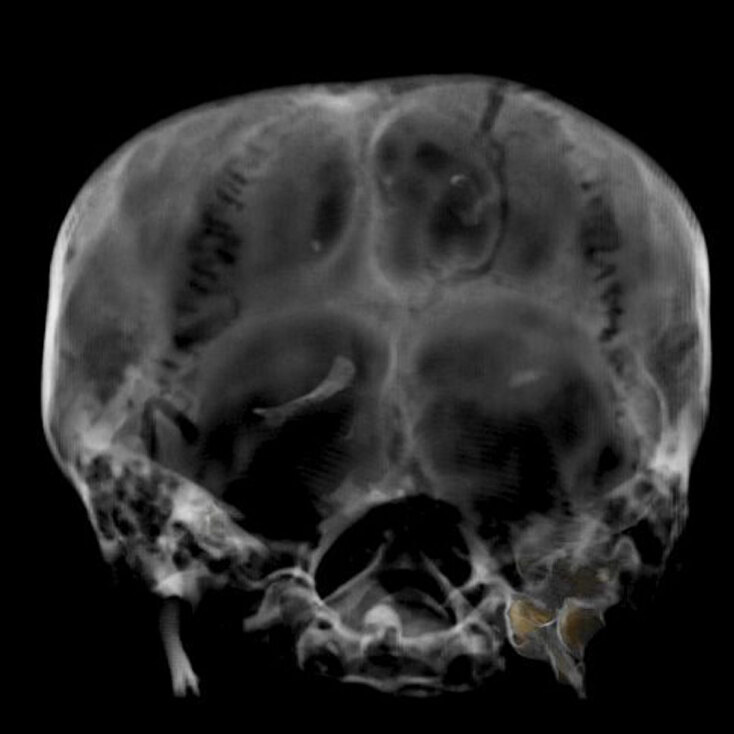

Στο ερώτημα «από τι πέθανε ο Τουταγχαμών» οι απόψεις διίστανται: Ατύχημα ή δολοφονία;. Κατά την εξέταση της μούμιας με ακτίνες Χ βρέθηκε μια κρανιοεγκεφαλική κάκωση, ωστόσο οι επιστήμονες δεν έχουν καταφέρει να πουν με βεβαιότητα αν είναι προϊόν κάποιας κληρονομικής ασθένειας ή δολοφονικό χτύπημα έπειτα από συνωμοσία σε βάρος του φαραώ.

Ακτινογραφία του κεφαλιού της μούμιας του Τουταγχαμών

Ακτινογραφία του κεφαλιού της μούμιας του Τουταγχαμών © EPA